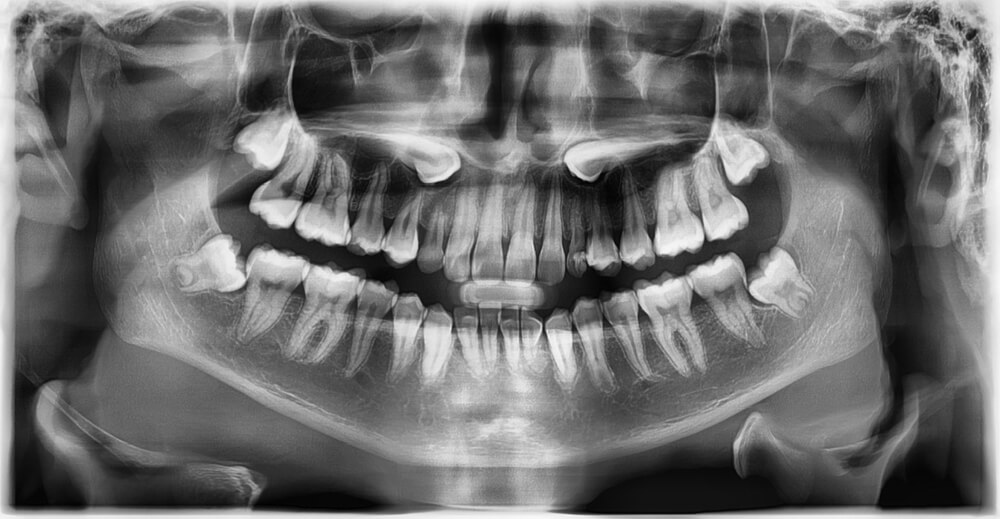

Gömülü dişler, kemik içerisinde yer almakta ve kişiler tarafından kolay bir şekilde fark edilmemektedir. Ağız içerisinde görünmediklerinden dolayı diş hekimi kontrolleri sonucunda tespit edilmektedir. Dişlerde sırasında eksik bir diş varsa bu dişin gömülü kalma ihtimali oldukça yüksektir. Tamamen kemik içerisinde duran ve hiçbir sorun oluşturmayan ve ağız içerisinde yeterli alan bulunan gömülü dişlerin alınmasına gerek duyulmamaktadır.

Her kurumun veya kliniğin kendisine has bir fiyat prosedürü olduğu için gömülü diş fiyatlarına ilişkin net bir sayı vermek oldukça güçtür. Gömük diş çekimi öncesinde röntgen, ameliyat ve normal çekim kararının fiyatlarına dair önceden görüşme yapılmalıdır. Özellikle diş çekimi öncesinde uygulamanın yapılacağı merkezde ön görüşme için muayene olmak gereklidir.